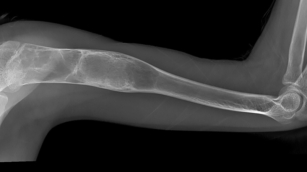

Bone Cysts and Tumors